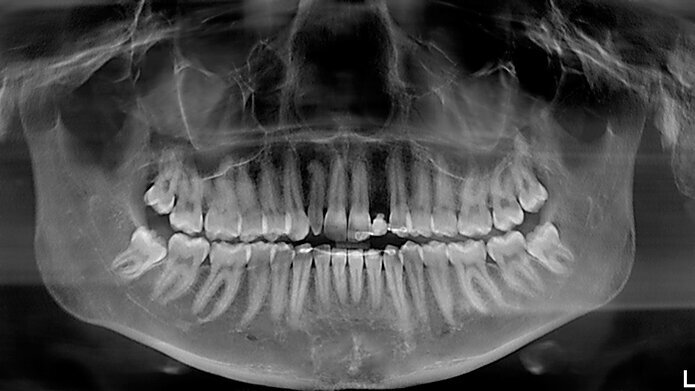

Fig. 1 - OPT delle arcate dentarie, si noti anomalia di forma elemento 12 e sito edentulo in sede 22.

Una ragazza di 20 anni si è presentata alla nostra attenzione con agenesia di elemento 22 ed elemento 12 con corona di conformazione conoide. Il sito edentulo in zona 22 si presenta riabilitato con una protesi tipo Maryland (Figg. 1, 2). La paziente dal punto di vista medico generale non presentava controindicazioni al trattamento implantare. È stata valutata tramite un approccio multidisciplinare ortodontico e implantare, al fine di ottenere la migliore integrazione estetica e funzionale della riabilitazione. Dopo aver valutato le alternative terapeutiche, si è deciso per una riabilitazione di tipo protesico su supporto implantare per il sito 22 edentulo e veneer in ceramica per l’elemento 12. La paziente si presenta da noi a crescita scheletrica ultimata quindi è possibile procedere con la riabilitazione implantare. Se gli impianti venissero inseriti in fase di crescita, infatti l’osso alveolare circostante potrebbe continuare a svilupparsi verticalmente e ugualmente i denti adiacenti potrebbero continuare a erompere, creando una discrepanza poco estetica tra il margine gengivale dell’impianto, quello dei denti naturali e una infraocclusione dell’elemento dentale su impianto9.